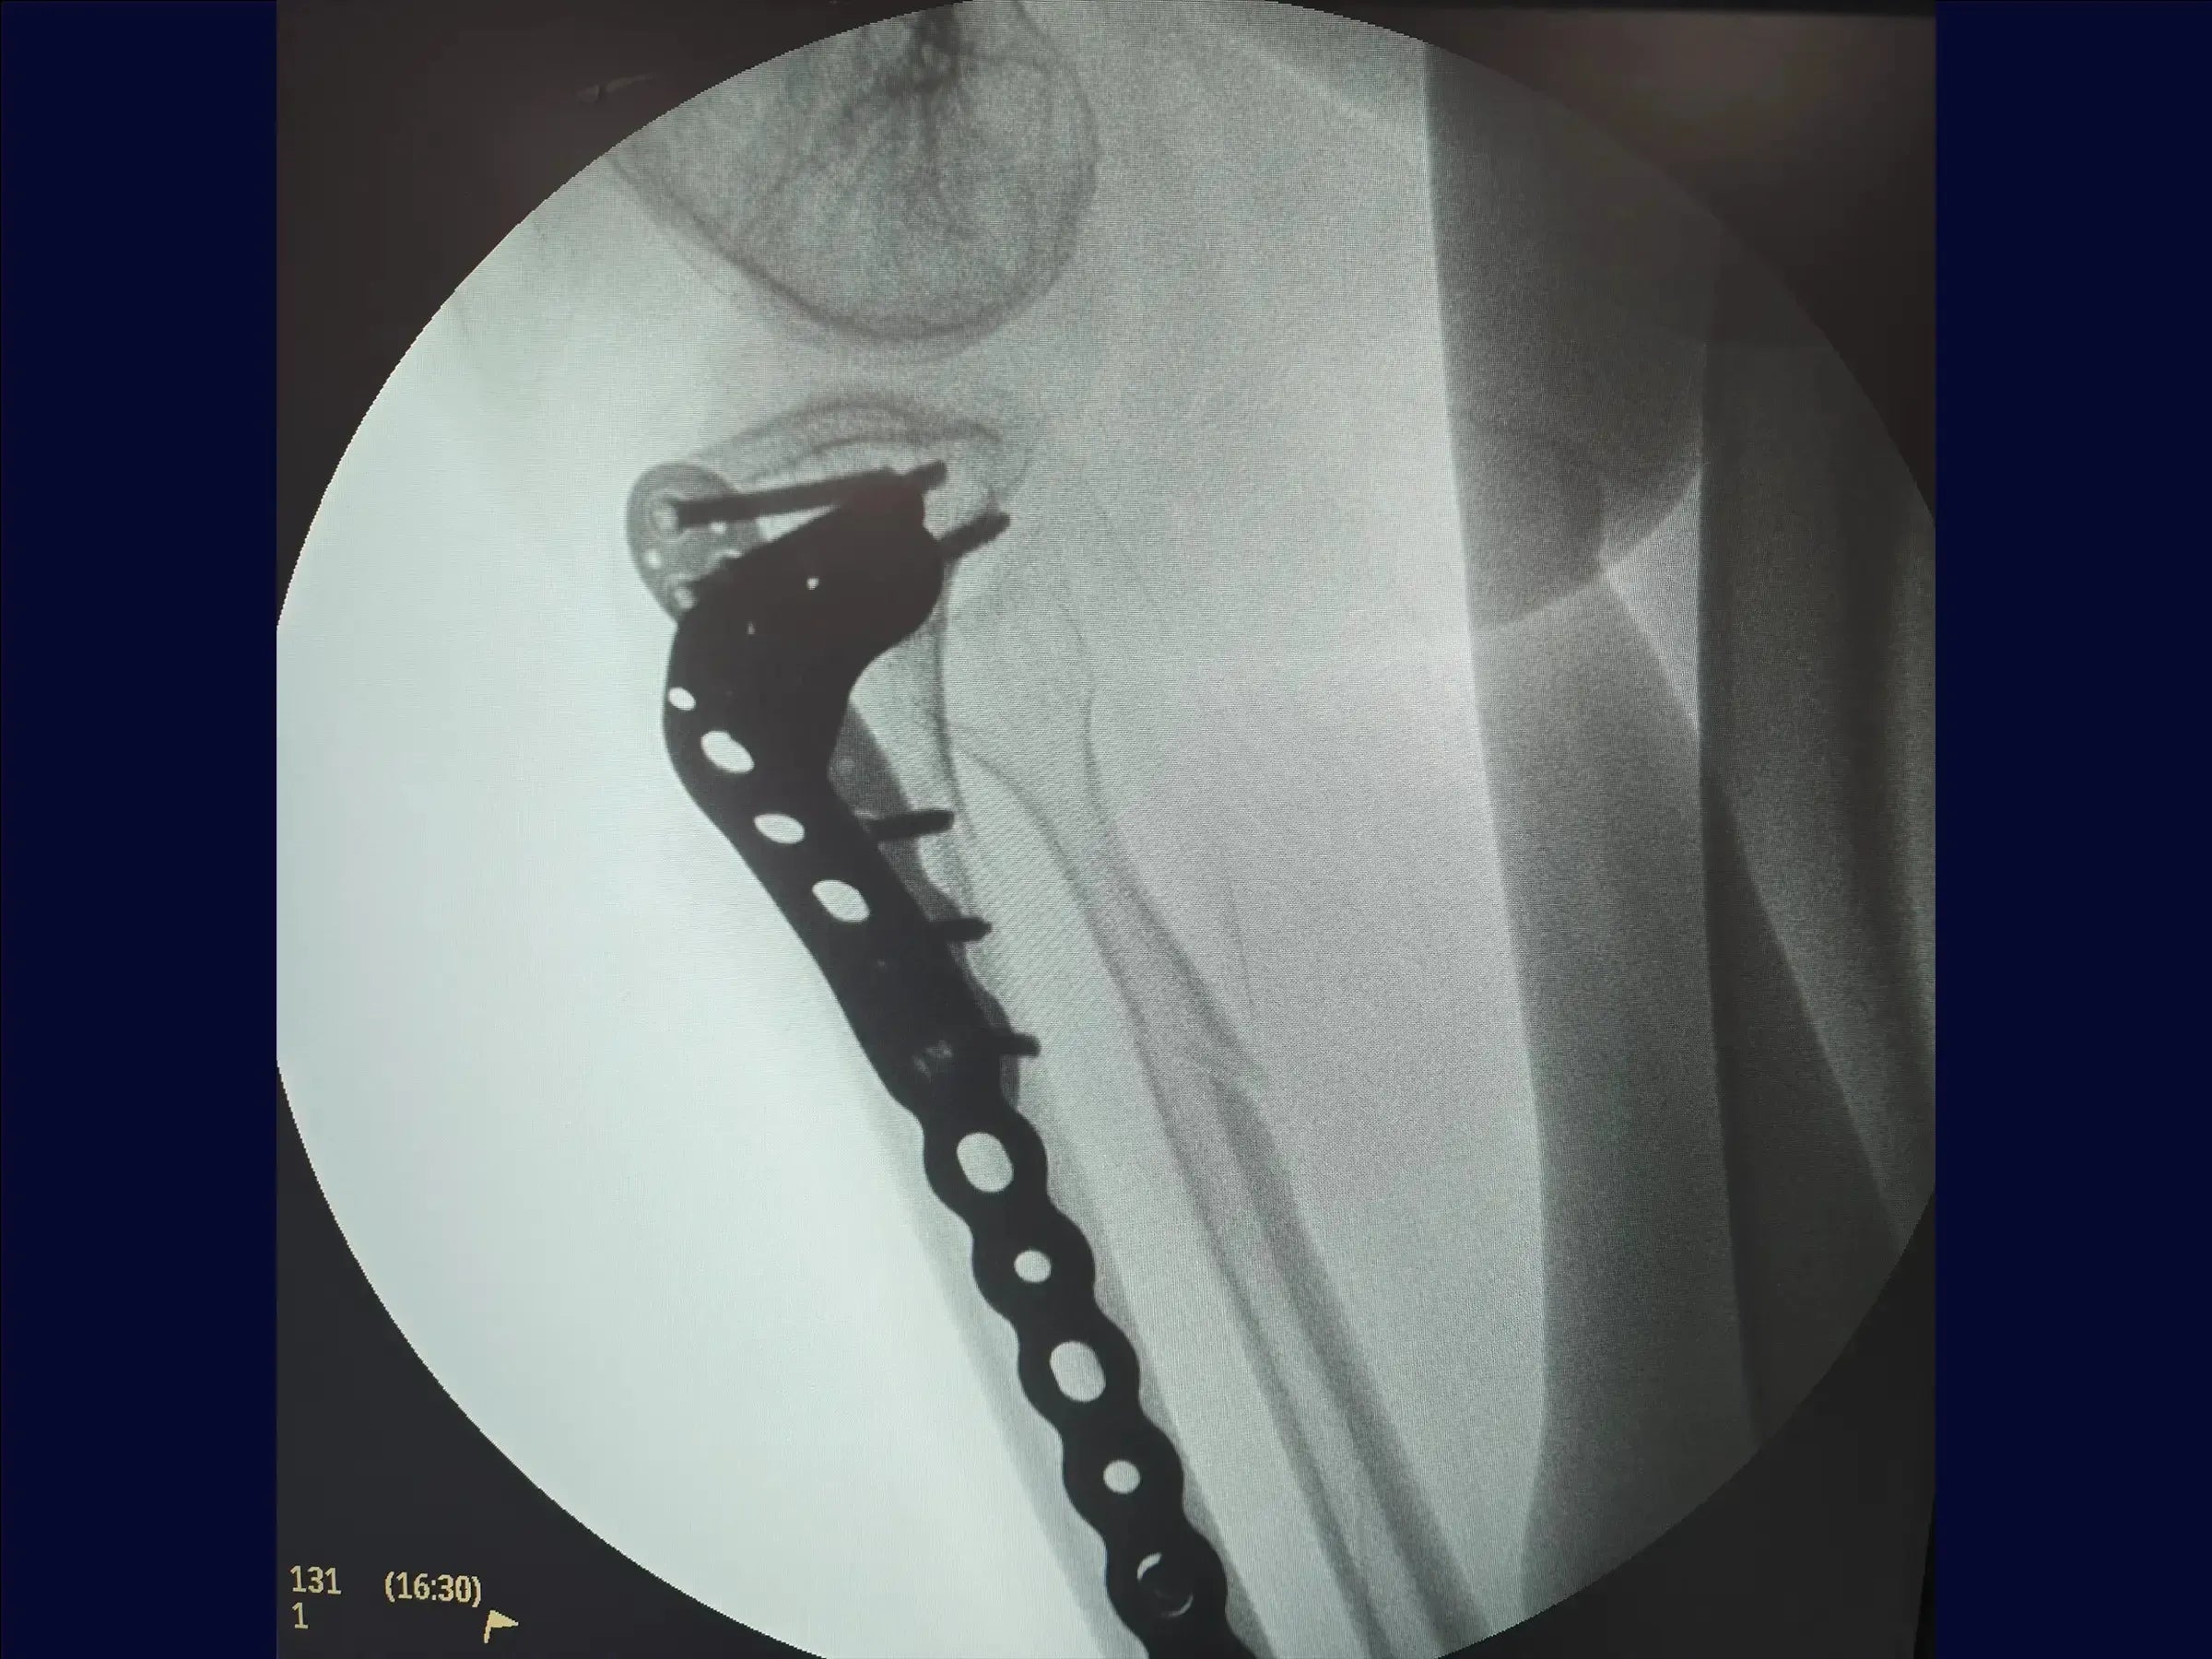

- Lateral approach with molded bridge plate.

- Lateral Bridge Plate Implantation: Submuscular tunnel technique using dissector and digital palpation to avoid intramuscular insertion.

- Tibial Curvature Plate Modeling: Custom adaptation with a table modeler to avoid protrusions.

- Stable Fixation with Cortical and Locked Screws: Strategic combination for torque, stability, and load distribution.

- Minimally Invasive Surgery with Dual Column Fixation: Anatomical reduction and biomechanical stability for low-density bones.